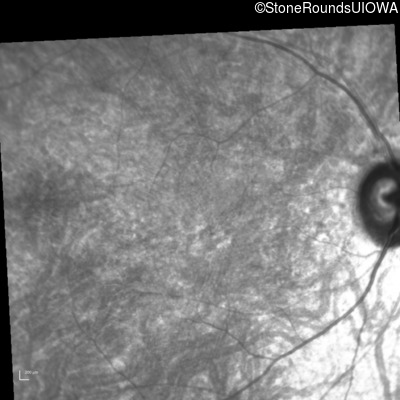

Infrared Fundus Photograph - Right - 10/200 -2 sc

Exemplar

Infrared Fundus Photograph - Left - 10/200 sc